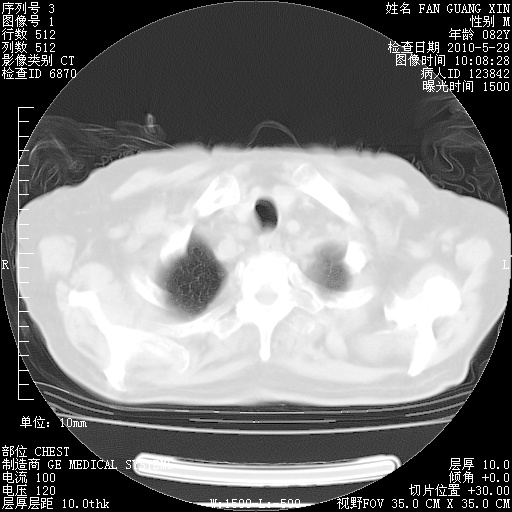

治疗3周后的肺部CT纵隔窗

再治疗10天后的肺部CT

再治疗10天后的肺部CT 纵膈窗